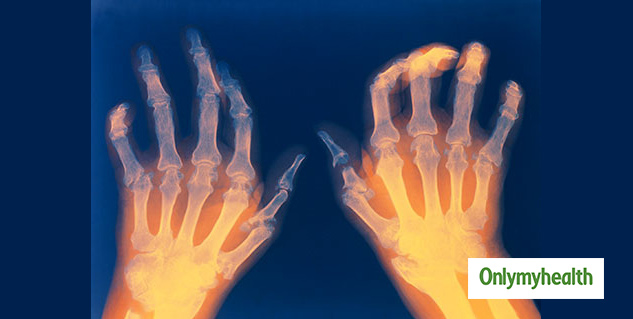

अर्थराइटिस में जोड़ों में सूजन आ जाती है, जिसके कारण मरीज को चलने-फिरने में परेशानी होने लगती है। आज के शहरी लोग बिल्कुल गतिहीन हो गए हैं, जिसका बुरा असर उनके मांस और हड्डियों की ताकत पर पड़ता है। आज अर्थराइटिस (खासतौर पर घुटनों का अर्थराइटिस) महामारी का रूप ले रहा है। उम्र के साथ होने वाला अर्थराइटिस ऑस्टियोअर्थराइटिस कहलाता है। भारत में ऑस्टियोअर्थराइटिस आमतौर पर 55-60 की उम्र में होता है, लेकिन आज कम उम्र में भी लोग अर्थराइटिस और अपंगता का शिकार बन रहे हैं।

डॉ. राठोर ने कहा कि अर्थराइटिस का सबसे आम प्रकार है ऑस्टियोअर्थराइटिस : इसका असर जोड़ों, विशेष रूप से कूल्हे, घुटने, गर्दन, पीठ के नीचले हिस्से, हाथों और पैरों पर पड़ता है। ऑस्टियोअर्थराइटिस आमतौर पर कार्टिलेज जॉइन्ट में होता है। कार्टिलेज हड्डियों की सतह पर मौजूद सॉफ्ट टिश्यू है, जो अर्थराइटिस के कारण पतला और खुरदरा होने लगता है। इससे हड्डियों के सिरे पर मौजूद कुशन कम होने लगते हैं और हड्डियां एक दूसरे से रगड़ खाने लगती हैं। अर्थराइटिस के लक्षण इसके प्रकार पर निर्भर करते हैं। इसमें दर्द, अकड़न, ऐंठन, सूजन, हिलने-डुलने या चलने-फिरने में परेशानी होने लगती है।